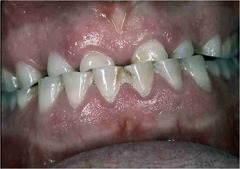

NUG/NUP

Front

-punched out, blunted papillae -painful, foul odor, metallic taste -regional lymphadenopathy

Back